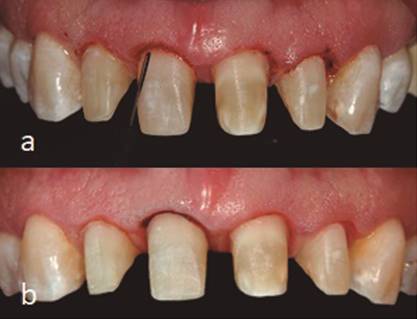

A los siete días (1 septiembre) se realizó retiro de suturas, se observó clínicamente la zona tratada desinflamada, del mismo color de la mucosa adyacente y sin signos de infección (Figura 5a). A las tres semanas de la cirugía se prepararon los dientes y se colocaron los provisionales (Figura 5b) y a las cinco semanas (30 septiembre) se realizó un recontorneo gingival con ayuda de electrobisturí (Figura 6a). A las nueve semanas se observó una adecuada cicatrización y se procedió a hacer toma de impresión (Figura 6b). El 2 de febrero se colocó la restauración final, observando tejidos sanos y estéticos (Figura 7). Mediante el procedimiento quirúrgico se logró la corrección y restablecimiento de los márgenes gingivales según los requerimientos protésicos, se obtuvo además la longitud coronaria deseada en la planeación del diseño de sonrisa. La realización de recontorneo gingival con electrobisturí permitió crear cénits más armoniosos y ayudó a crear mayor simetría en los márgenes gingivales. La paciente expresó sentirse contenta con los resultados finales tanto de la cirugía como de la colocación de las carillas.